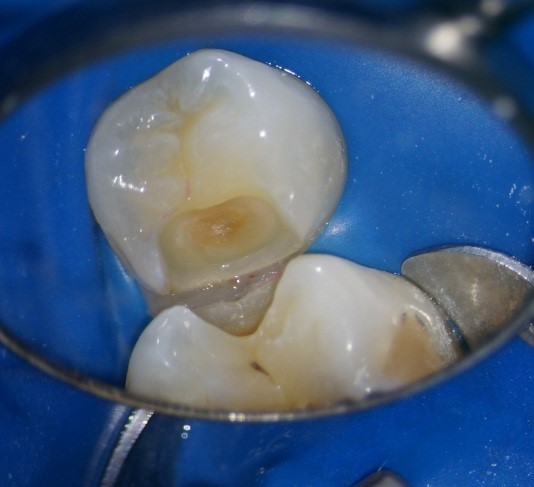

Пример лечения зуба со скрытой кариозной полостью(неосложненная форма).

После удаления эмали размер кариозного процесс становиться более очевидным.